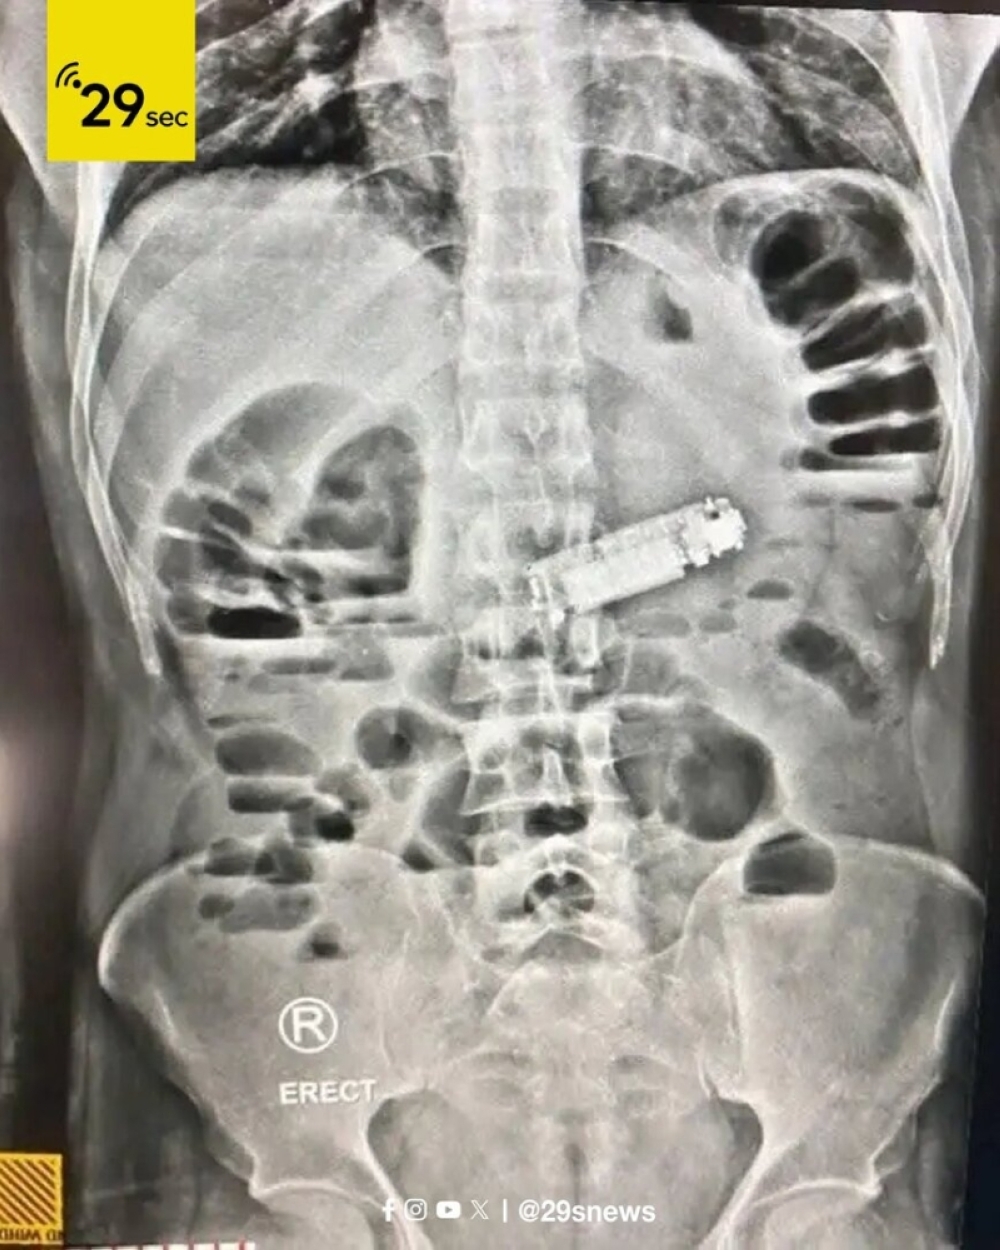

وذكرت مديرية الصحة بالبحر الأحمر أن المريض وصل إلى المستشفى في حالة طارئة، يعاني من إعياء شديد وقيء متواصل وآلام حادة في البطن. وعلى الفور أُجريت له الفحوصات الطبية والأشعة اللازمة التي كشفت عن وجود جسم غريب داخل المعدة يعيق مرور الطعام، ليتضح أنه هاتف محمول صغير.

عقب التشخيص، باشر الفريق الطبي تنفيذ عملية جراحية عاجلة ودقيقة لاستخراج الهاتف، حيث تمت العملية بنجاح ودون أي مضاعفات. وأكد المستشفى أن المريض استعاد وعيه فور نقله إلى قسم الإفاقة، وحالته الصحية مستقرة حاليًا، فيما يخضع للملاحظة الطبية للتأكد من سلامته.